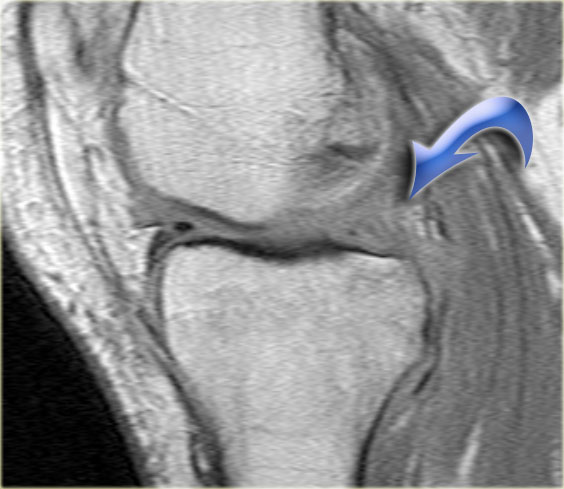

Như bạn đã đoán được qua tiêu đề của đoạn này, đây là một trường hợp sụn chêm lật (flipped meniscus).

Sụn chêm lật là một dạng đặc biệt của rách dạng quai xô (bucket-handle tear).

Sụn chêm lật xảy ra khi mảnh vỡ của sừng sau bị lật ra phía trước, khiến sừng trước của sụn chêm có vẻ to hơn bình thường.

- Sừng sau quá nhỏ và sừng trước có vẻ to hơn với đường viền không đều.

- Thoạt nhìn có vẻ như có một đường rách dọc ở sừng trước, nhưng thực chất phần sau của cấu trúc này chính là phần lật của sừng sau bị rách.

Cấu trúc phía trước là sừng trước.

Cũng cần lưu ý tình trạng phù tủy xương khu trú và dấu ấn lõm sụn khớp. - Cấu trúc phía trước là sừng trước.